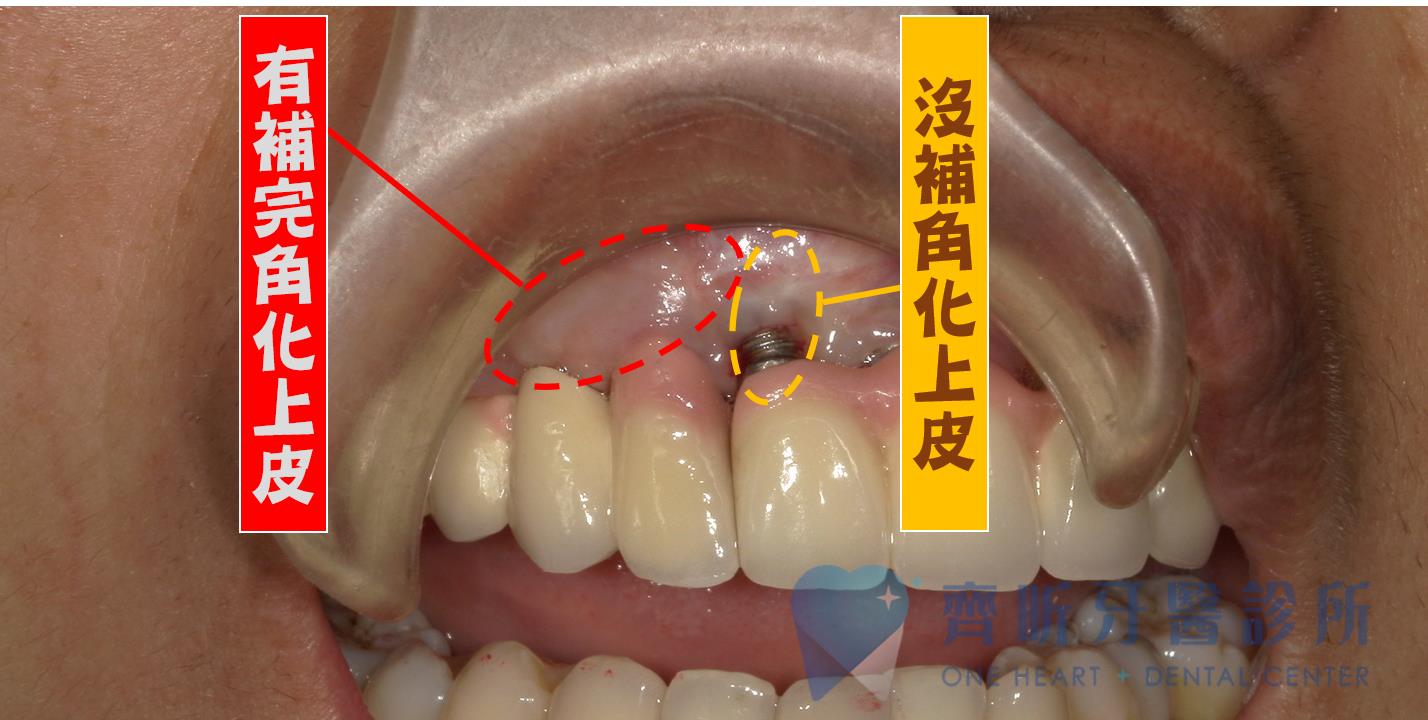

同一個患者在做過上皮移植的情況下,

明顯可以看到多年後植牙是一樣的健康,

周圍組織仍是非常堅固。

反觀沒有做過上皮移植的區域 (之後別的醫師種植的植牙),不只發生牙齦萎縮、出血、骨頭萎縮、植體暴露、散發異味…等等,也大大減少植體的壽命。在短短兩年內植牙就壽終正寢了。